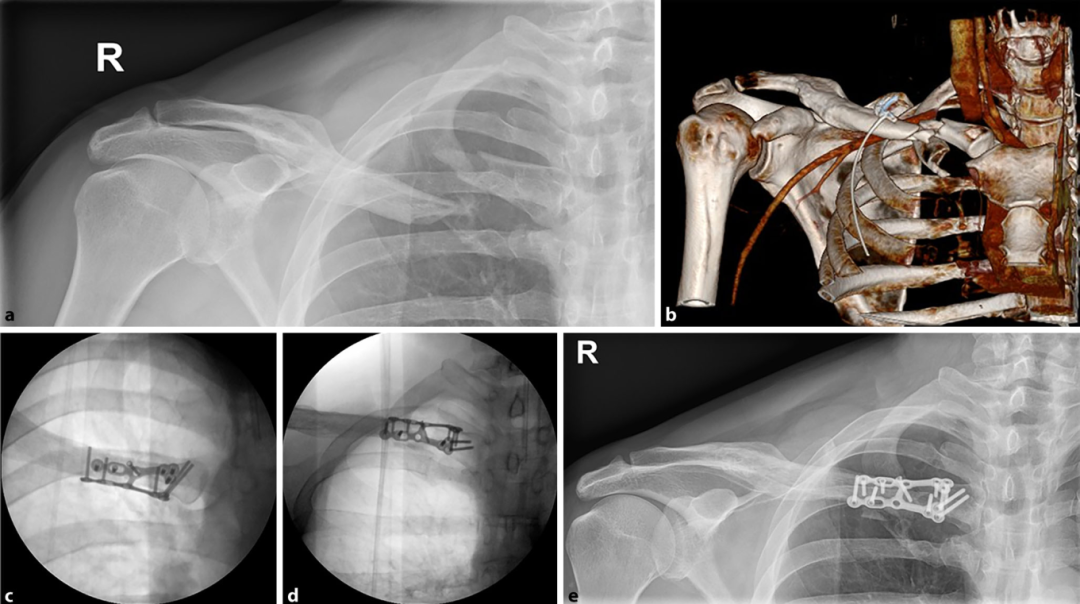

锁骨内侧端骨折占锁骨骨折的2-3%,多见于高能量暴力损伤,常合并胸部创伤。无移位的、稳定的锁骨内侧端骨折,通常采取保守治疗;对移位不稳定的,且上肢功能要求较高的患者,可考虑手术治疗。对于锁骨内侧端骨折,目前内固定方式众多,包括锁骨远端钢板、胸锁关节解剖钢板、钢丝固定、T-形钢板固定等:

由于锁骨内侧软组织较薄弱,采用3.5/2.7mm钢板螺钉系统内植物容积较高,容易出现局部激惹甚至需取出内固定。为此,国外学者利用桡骨远端背侧钢板,塑形为双平面呈“90°”的新型内固定,内植物激惹小,疗效良好:

锁骨内侧端骨折目前最常用的内固定仍是T型钢板固定,尽管有生物力学研究表明,前方、上方双钢板固定具有更好的稳定性,但考虑到经济因素,仍是单钢板居多。因此,文中介绍的桡骨背侧钢板折弯的巧妙使用,可能值得骨科医师借鉴。